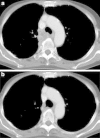

Results: On histologic review of the malignant epithelial component, adenocarcinoma was identified in seven cases (43.8%), large cell carcinoma in four (25.0%), and squamous cell carcinoma in two (12.5%). For the sarcomatoid component, 14 cases (87.5%) had both spindle cell tumor and giant cell and 2 (12.5%) had giant cell. Eleven patients received cytotoxic chemotherapy as first-line but did not achieve an objective response, although one patient who received docetaxel as second-line achieved a partial response. We also found that one patient achieved long stable disease of about 9 years without progression after receiving cisplatin and gemcitabine treatment. EGFR mutation, KRAS mutation and ALK expression were investigated in 14 patients whose tumor specimens were available. EGFR mutation was observed in 2 (14.3%) and KRAS mutation in 3 (21.4%), while no patient was positive for ALK expression. One patient harboring EGFR exon 19 deletion was treated with gefitinib after postoperative recurrence and achieved a complete response of about 35 months.

Conclusions: Although advanced PPC showed a poor response to chemotherapy, one patient with EGFR mutation achieved an extended complete response. We therefore recommend the evaluation of driver gene alteration such as EGFR in the treatment of advanced PPC.